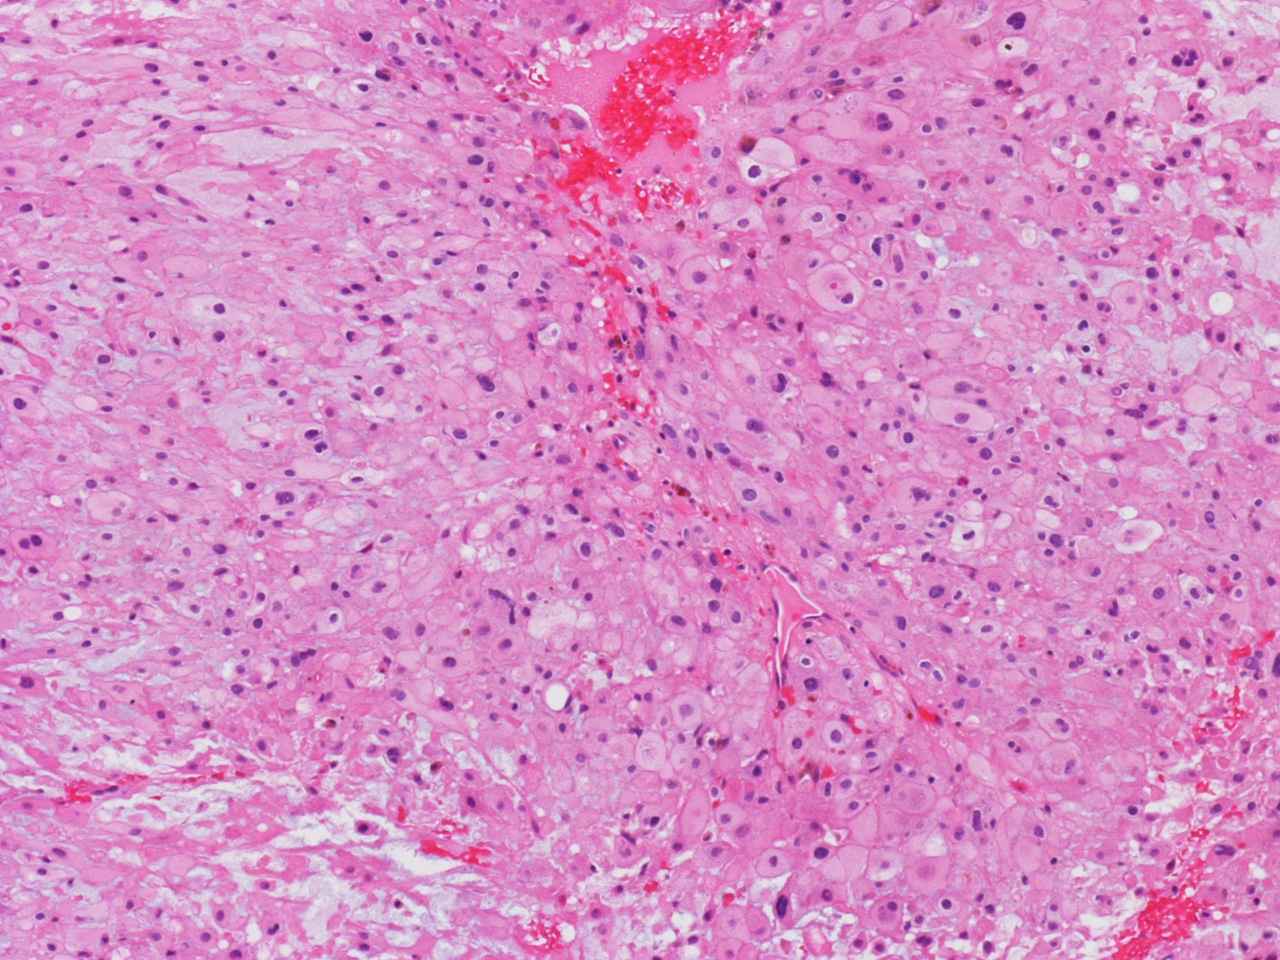

At the time of operation, a cytologic squash preparation (H&E) was prepared (Panels BC, and D). On low magnification, the lesion is composed of large clusters of eosinophilic cells with centrally located nuclei. There is some bluish acellular substance admixed with the tumor cells (Panel B). If you pay attention, some of the cells are arranged in short chains (arrows in Panel C). This is a frequently seen phenomenon in chordoma. On high magnification, the cells have centrally located medium sized to large, hyperchromatic nuclei. The cytoplasm is finely eosinophilic but not particularly bubbly  (Panel D). The frozen sections (Panels E and Freflect the cytologic features. The tumor is composed of solid sheets of large tumor cells admixed with small amount of fibrous areas, mild chronic inflammatory cell infiltration and hemosiderin depositions (Panel E). On high magnification, the tumor cells are admixed with bluish extracellular material.  The cytoplasm is coarsely granular with fine bubbles. The permanent sections (Panel G and Hshow similar features. And the bubbly cytoplasm is more prominent in the permanent sections (Panel H). Focal bone invasion is present (Panel I). The cytoplasmic vacuoles are best appreciated in the semithin section (Panel M). Results of special studies are as follows:

The characteristic histologic findings in chordomas are large polygonal cells with distinct cell membrane and the vacuolated physaliphorous cytoplasm, the term deriving from the Greek physalis, or "bubble. The vacuolated or physaliphorous cells are best appreciated in cytologic smears or squash preparations. Tumor cells grow in small nests and cords within a myxoid/chondroid matrix and demonstrate round, sometimes rather uniform nuclei with low nuclear-to-cytoplasmic ratios. The tumor cells tend to adhere into clusters and cords. The classic large physaliphorous cell has a centrally located nucleus surrounded by a narrow rim of cytoplasm that in turn, is encircled by a ring of more peripherally located cytoplasmic vacuoles. Nuclear grade is not particularly high in some cases but many of them have clearly recognizable nuclear pleomorphism. Occasional large, atypical cells are present. These nuclear changes should not be present in benign notochordal cell tumor and ecchordosis physaliphora/fetal vestige [Amer & Hameed, 2010]

On cytologic smears [Crapanzano JP et al., 2001], chordoma cells tend to be cohesive but not as cohesive to each other as carcinomas. Strings of chordomas are common features.